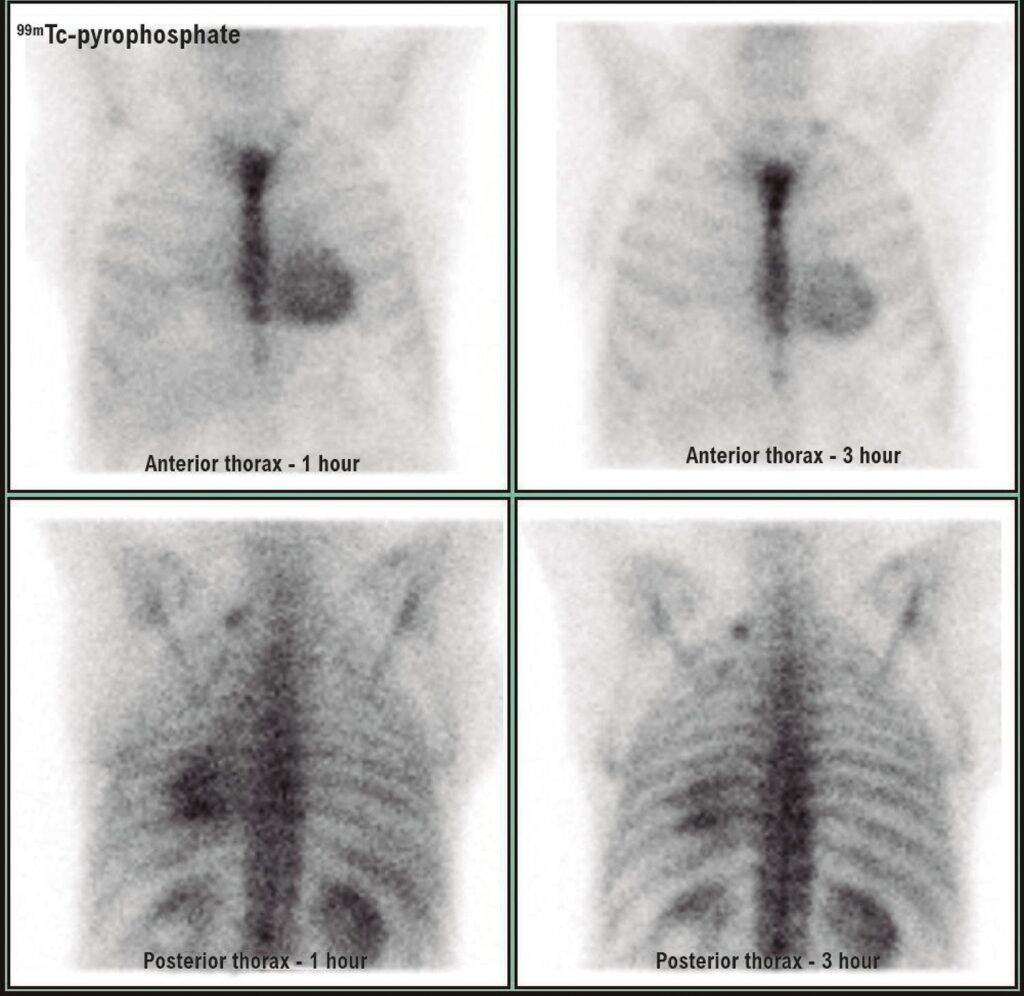

Aortic stenosis is the most prevalent valve disease in clinical practice. The wild form of transthyretin amyloidosis has an increased incidence in elderly individuals, usually over 70 years of age. Amyloidosis and aortic stenosis are 2 diseases that affect similar populations; therefore, they may coexist in the same patient.

Patients with amyloidosis and aortic stenosis have disproportionately higher serum levels of troponin and NT-proBNP compared to patients with pure severe aortic stenosis in addition to greater ventricular hypertrophy. Therapeutic decisions for these patients must be individualized and promptly discussed by the heart team. In this article, we discuss this association and possible valve therapies, in addition to the possibility of specific treatment for amyloidosis.